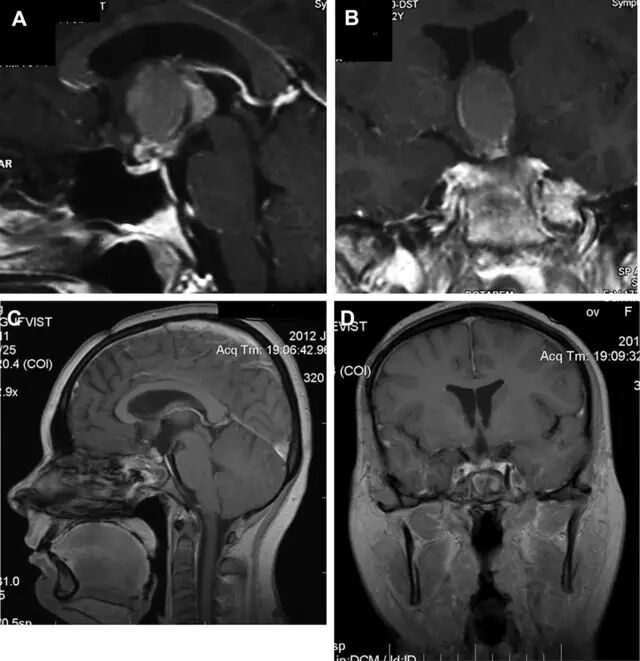

图 3 术前增强磁共振成像(A,B)显示鞍上颅咽管瘤。术后矢状位(C)和冠状位(D)增强磁共振成像显示肿瘤完全切除